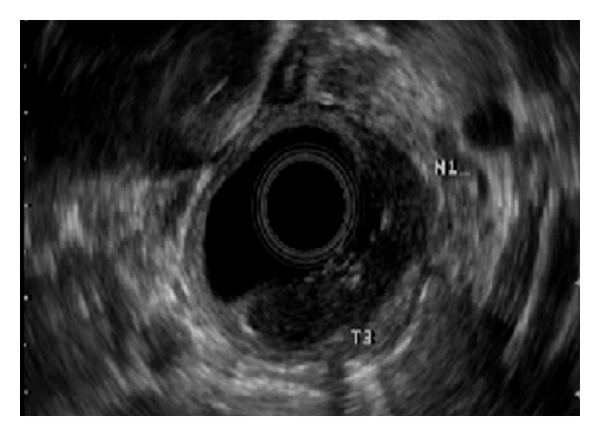

A 46-year-old Caucasian woman with no significant past medical or family history presented to her primary care provider with a one-year history of sore throat and dysphagia to solid foods. She reported a remote smoking history in her teens and rare alcohol consumption. Workup included a barium swallow study with a persistent filling defect in the upper esophagus measuring 5 cm 1.8 cm originating from the posterior right wall of the esophagus. Differential diagnosis included both benign and malignant lesions of the upper esophagus. Upper endoscopy with endoscopic ultrasound revealed an ulcerated, friable mass extending from 15 to 19 cm from the incisors with evidence of invasion into the muscularis propria and suspicion for regional node involvement (Figures 1(a) and 1(b)). Biopsies from the upper endoscopy were positive for moderately differentiated invasive adenocarcinoma (Figures 2(a) and 2(b)).

(a)

(b)